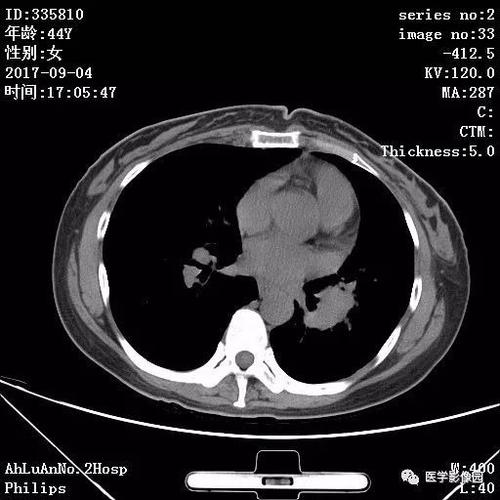

影像技术:肺结节的良恶之辨在现代医学领域,影像技术的发展已成为诊断和治疗疾病的重要手段。特别是在肺部疾病的诊断中,影像技术的应用已经达到了前所未有的高度。刘波教授,一位在影像学领域有着深厚造诣的专家,提出了一个引人深思的问题:肺结节是否等同于癌症?哪些肺结节会癌变?刘波教授指出,影像技术的进步使得肺结节的检测和分析变得更加精准。例如,超声及核医学等技术在临床上的应用,已经能够对肺结节进行更为细致的评估。这些技术不仅提高了疾病的诊断准确率,也为后续的治疗提供了重要依据。然而,面对众多的影像检查手段,如何选择最合适的检查方法,以及如何解读影像报告,是广大患者和医生需要共同面对的问题。刘波教授强调…